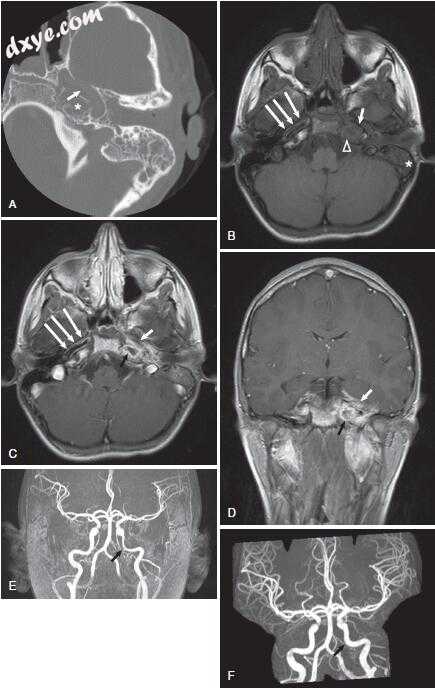

图-11. 影像学表现为左侧岩尖炎。 A,颞骨骨骼计算机断层扫描显示左颞骨岩尖炎。注意岩骨顶端的浑浊与骨质隔膜(星号)的破坏。在这个对比研究中也可以看到颈动脉管的裂开和岩骨颈动脉的狭窄(箭头)。 B,轴位非对比增强T1加权磁共振成像(MRI)显示乳突浑浊(星号)。与右侧看到的亮脂肪信号相比,左侧岩尖也是不透明的(箭头)。注意左侧颈内动脉狭窄口径(ICA;短箭头)与右侧ICA(箭头)相比。 C,轴向造影增强T1加权MRI在左侧岩尖处显示低信号,周边对比度增强(黑色箭头)与炎症一致。注意左侧ICA的窄口径(短箭头)与右侧的ICA(箭头)相比较。 D,冠状位造影增强T1加权MRI在左侧岩尖部显示低信号,周边对比度增强(黑色箭头)。注意增强毗邻岩尖的硬脑膜和颞叶(白色箭头)。 E,治疗前患者的MR血管造影(MRA)显示左侧岩石ICA变窄(箭头)。 F,随访MRA显示缩小后的ICA正常口径(箭头)。